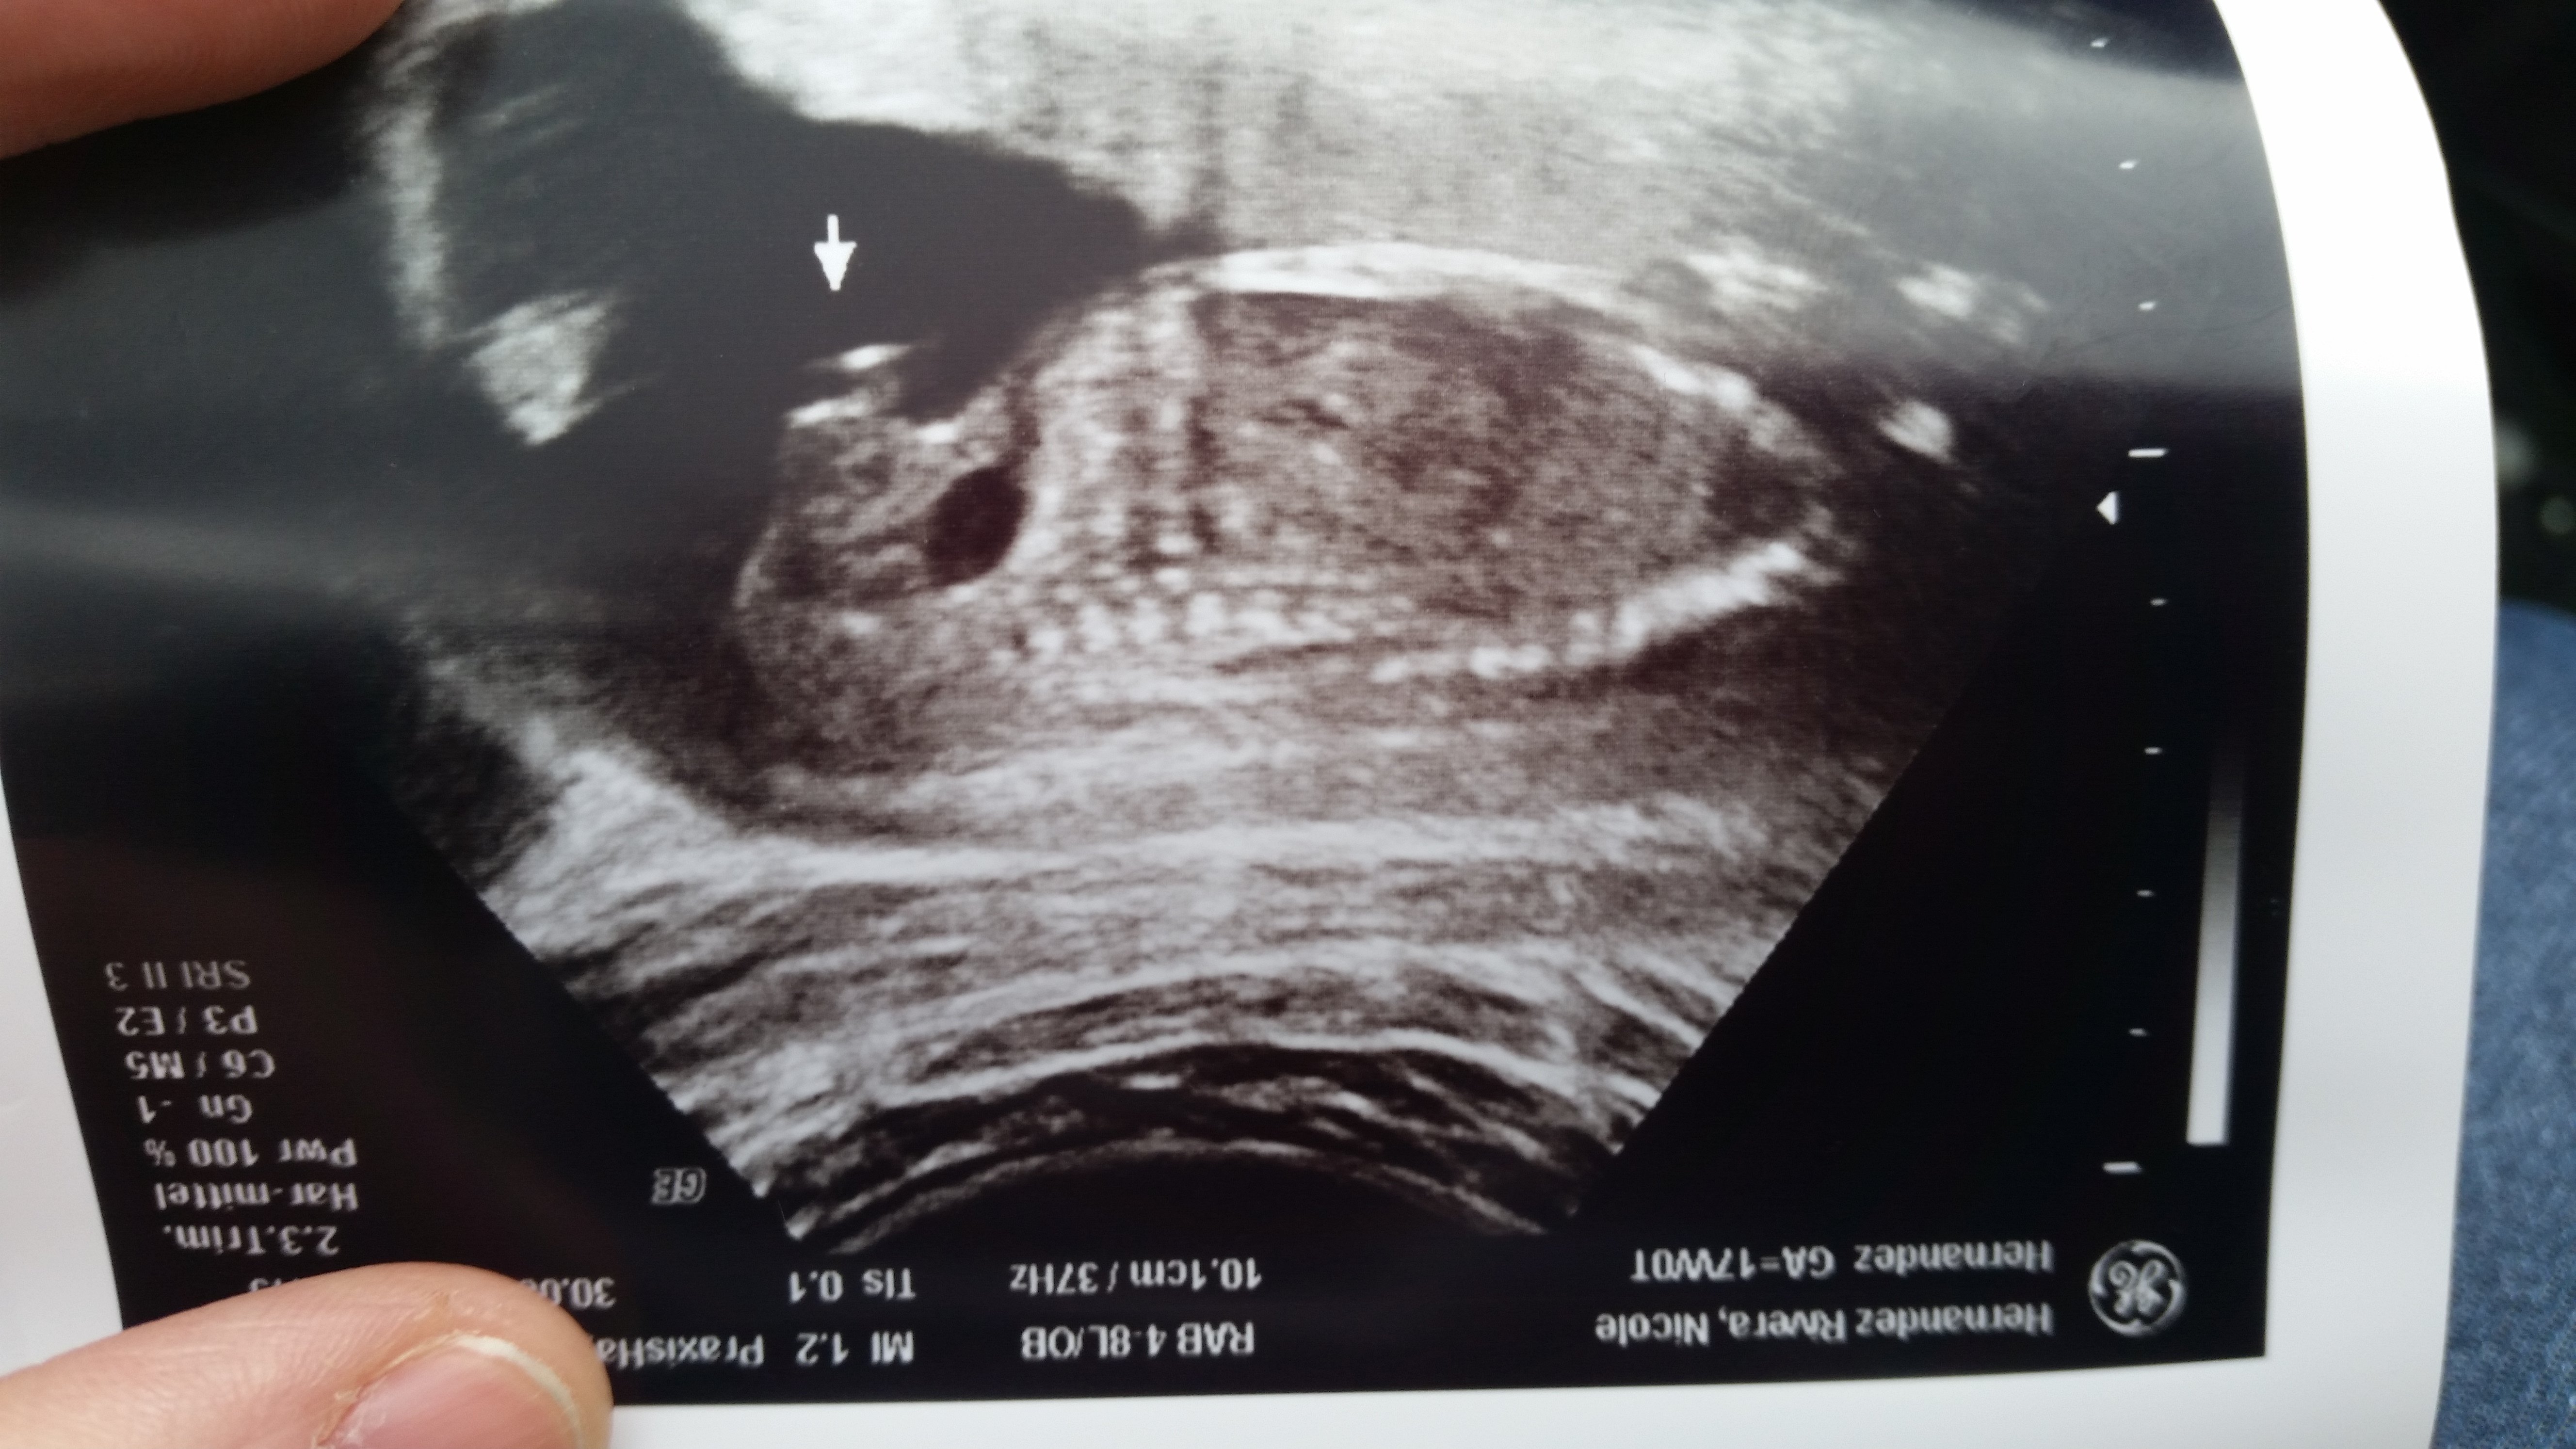

Anatomy scan picture at 20 wks!! Or is there any way this could be a girl?? Thank you!!

17 wks US Attachment 32654

17 wks potty shot Attachment 32655

Thank you!!! Do you see his boy parts in the first image I posted?? I had a Dr. Last week that told me baby was a girl cz he saw three lines, but even boys can image as 3 lines depending on their position so he kinda threw me off..

The 1st pic is from the anatomy scan and tech told me Boy.. I should just go with it and forget what that Dr. Said right??

Yes I see Boy bits in the first image as well! Not much of a penis in that particular angle but definitely the scrotum! And yes boys can very much so, image 3 lines! My cousin had a baby boy in 2015 who was predicted to be a girl at first due to 3 lines... I'll draw on your first image here in a bit when I get on my PC again ;) no worries tho' without a doubt team blue xx

Here's how I see it... It's not the best image to guess gender off of, that's for sure, but there is nothing girly about it! the 3 lines the tech referred to do not represent labia and clitoris here.